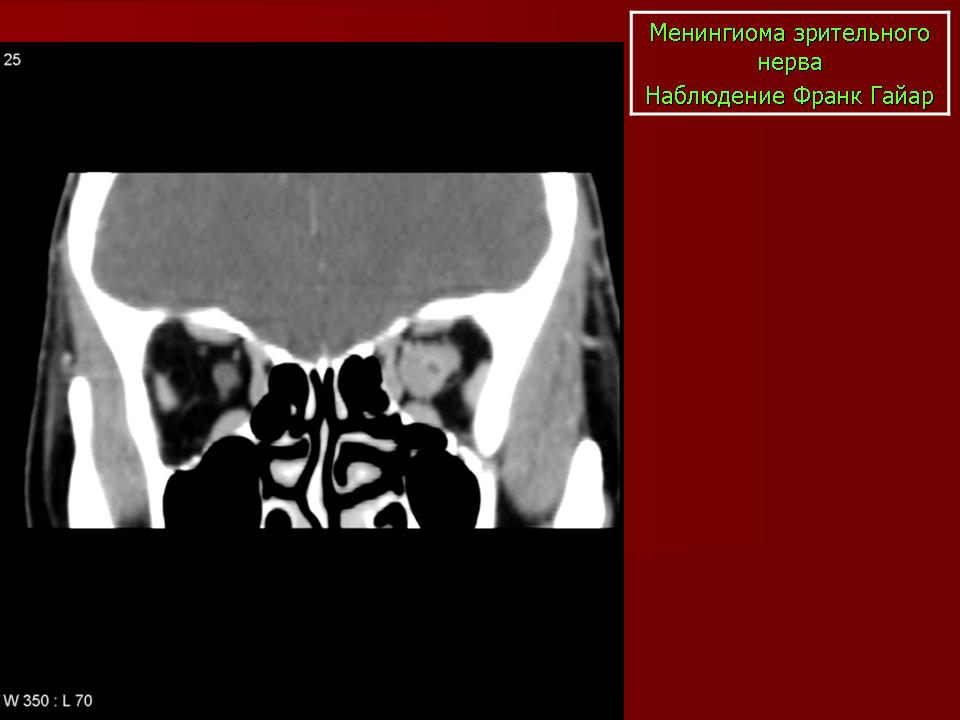

КТ-семиотика

На КТ срезах без контрастного усиления менингиома зрительного нерва выглядит изоденсной. Типично наличие линейных или точечных обызвествлений. Симптом «трамвайных рельс» отражает накопление КВ по сторонам гиподенсного зрительного нерва или наличие обызвествлений в структуре опухоли. Как правило, наиболее дистальная часть зрительного нерва, в месте его вхождения в глазное яблоко, не содержит обызвествлений.

Наиболее типичная черта: объемное образование, расположенное вдоль интраорбитальной части зрительного нерва, накапливающее КВ и содержащее обызвествления по типу трамвайных рельс. Форма: тубулярная (65%) > на ножке (25%) > веретеновидная (10%). Формируется вокруг нерва, реже растет эксцентрично или имеет ножку

При исследовании необходимо определить расположение бляшковидной менингиомы относительно бугорка турецкого седла и пластинки клиновидной кости, так как данный тип опухоли может распространяться интракраниально через канал зрительного нерва. КТ не позволяет адекватно визуализировать интракраниальное распространение опухоли, которое может привести к развитию двусторонней слепоты.